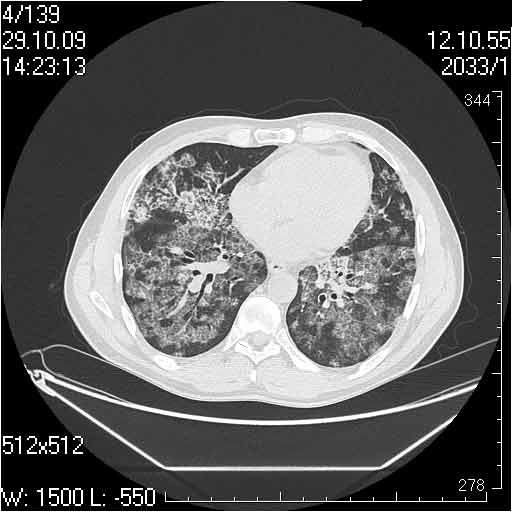

Случай №2

Мужчина 54 лет

Случай 2: картина патологических изменения довольно типична: GGOs & thickened interlobular septas = "crazy paving" sign. Наличие плотностей по типу матового стекла в сочетании с утолщением междолевых перегородок, даёт признак булыжной мостовой; на первом месте будет стоят диагноз альвеолярных протеиноз.